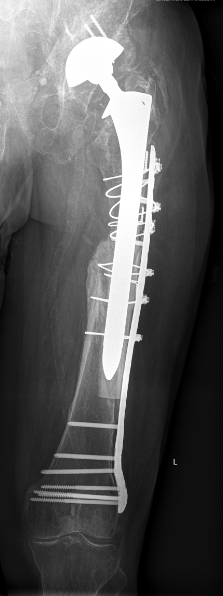

Minimal invasive Hüftgelenkersatz